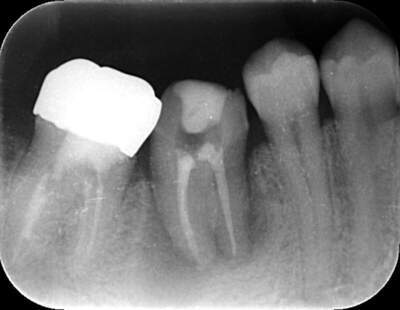

2021.4.3 定期検診時

この時はまだ症状がなかった

しかし歯は縦に割れており、いつ痛みが出てもおかしくないような状態であることは説明していた。

2022.1.15 根尖性歯周炎の急性化

疼痛ありで急患来院。

前々から爆弾抱えているような物で、何かあったら抜歯と伝えていた部位。以前よりクラウンマージン下で歯根縦破折であったが、症状なしで経過観察をおこなっていた。

抜歯予定とし、アモキシシリンとロキソニンを処方した。

2022.2.5 抜歯後の消毒

口腔内写真

CT画像

骨の状態はそこまで悪くないが、欠損が大きい。

レントゲン写真

根管治療後3ヶ月です。根のまわりの骨がやや白くなってきているのがわかります。だんだん骨の添加がみられている証拠になります。

ここまで治癒していればかぶせ物をかぶせても問題ないと判断しました。

最後のレントゲンでは、骨がしっかり添加され、周囲組織となんら変色ない状態にまでなっていることがわかる。